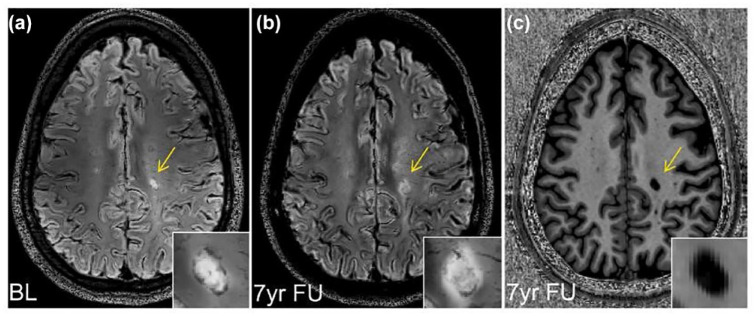

在多发性硬化症(MS)中,越来越多的残疾被认为是由于中枢神经系统(CNS)内持续的慢性炎症而发生的。这种情况被称为阴燃性神经炎症,存在于MS的临床谱中,目前被认为对现有的疾病改善疗法具有相对抗性。慢性活动性白质病变是阴燃性神经炎症的重要组成部分。最初以尸检标本为特征,使用先进的神经成像技术和后处理方法来可视化体内慢性活动性病变(CALs)的多种方法正在迅速出现。在这些与CALs相关的体内成像中,顺磁边缘病变(prl)是由富含铁的小胶质细胞和巨噬细胞形成的病灶周围边缘定义的,而缓慢扩张的病变是根据随时间的线性、同心扩张来识别的。近年来,一些纵向研究将体内检测到的CALs的发生与更具侵袭性的疾病病程联系起来。prl对多发性硬化症具有高度特异性,因此最近被纳入多发性硬化症的诊断标准。它们还具有作为生物标志物的预后潜力,可识别有早期和严重疾病进展风险的患者。这些进展可能会显著影响MS的护理和新疗法的评估。本文介绍了CAL生物学和影像学的最新知识,以及CAL与ms自然历史的相关性。此外,我们概述了当前和未来CAL体内生物标志物的考虑,强调了其评估的验证、标准化和自动化的必要性。

In multiple sclerosis (MS), increasing disability is considered to occur due to persistent, chronic inflammation trapped within the central nervous system (CNS). This condition, known as smoldering neuroinflammation, is present across the clinical spectrum of MS and is currently understood to be relatively resistant to treatment with existing disease-modifying therapies. Chronic active white matter lesions represent a key component of smoldering neuroinflammation. Initially characterized in autopsy specimens, multiple approaches to visualize chronic active lesions (CALs) in vivo using advanced neuroimaging techniques and postprocessing methods are rapidly emerging. Among these in vivo imaging correlates of CALs, paramagnetic rim lesions (PRLs) are defined by the presence of a perilesional rim formed by iron-laden microglia and macrophages, whereas slowly expanding lesions are identified based on linear, concentric lesion expansion over time. In recent years, several longitudinal studies have linked the occurrence of in vivo detected CALs to a more aggressive disease course. PRLs are highly specific to MS and therefore have recently been incorporated into the MS diagnostic criteria. They also have prognostic potential as biomarkers to identify patients at risk of early and severe disease progression. These developments could significantly affect MS care and the evaluation of new treatments. This review describes the latest knowledge on CAL biology and imaging and the relevance of CALs to the natural history of MS. In addition, we outline considerations for current and future in vivo biomarkers of CALs, emphasizing the need for validation, standardization, and automation in their assessment.